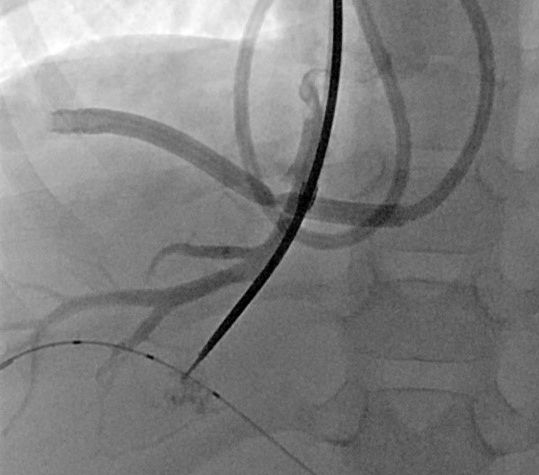

7 jähriger Junge mit Kurzdarmsyndrom und Leberzirrhose

Als Folgen des Pfortaderhochdrucks war die Milz vergrößert (Splenomegalie) und es traten Krampfadern der Speiseröhre (Ösophagusvarizen) auf. Um den Hochdruck zu entlasten wurde ein TIPS angelegt. Dazu wird aus der rechten Lebervene (A) mit einer speziellen Nadel ein Pfortaderast punktiert (B). Anschließend wird die Pfortader mit einem Draht sondiert (C) und die geschaffene Verbindung mit einem Ballon aufgedehnt und anschließend mittels Gefäßstütze (Stent) geschient (D). Durch diese künstliche Verbindung kann das Pfortadersytem deutlich druckentlastet werden.